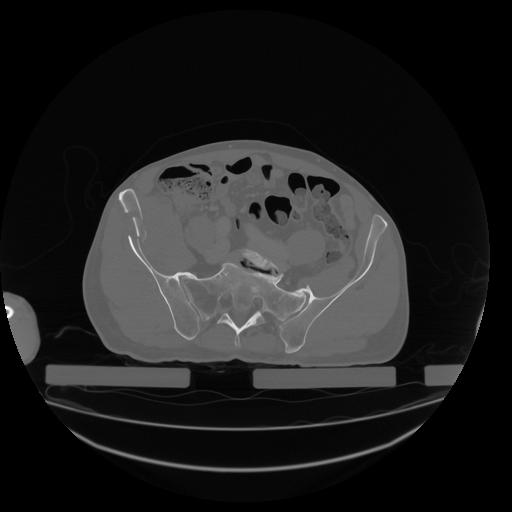

34 CUERPO,CE,Vol,1.0,CUERPO,,